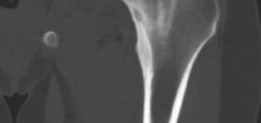

High-resolution, thin-slice computed tomography (CT) with multiplanar reconstruction is the gold standard for defining the osseous anatomy. The CT scan accurately delineates the nidus as a well-circumscribed, radiolucent focus, often containing a central fleck of mineralization, surrounded by varying degrees of sclerosis. The surgeon must meticulously map the location of the nidus relative to reliable arthroscopic landmarks, such as the medial synovial fold, the zona orbicularis, and the articular margin of the femoral head.

Following excision, the cavity is thoroughly irrigated to remove all osseous debris. Intraoperative fluoroscopy is repeated to confirm complete removal of the radiolucent nidus and to assess the size of the resulting cortical defect.

If the defect is small and located on the compressive side of the neck, no further intervention is required. However, if the resection violates more than 30% of the neck diameter, or if it is located on the superior tension side, the surgeon must strongly consider prophylactic internal fixation. This is typically achieved percutaneously using two or three parallel 6.5 mm or 7.3 mm cannulated screws placed over guidewires under fluoroscopic control.